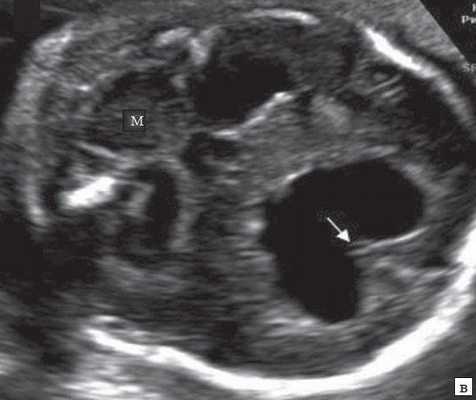

В наблюдениях 1-3 имело место расширение боковых желудочков до 14, 18 и 32 мм соответственно (рис. 5), 3-го желудочка - до 3,2 и 4,9 мм и отсутствие картины полости прозрачной перегородки (ПП). При этом в наблюдениях 2 и 3 отмечалось также нарушение срединных структур мозга и слияние лобных рогов. Мозолистое тело было выявлено в наблюдении 2, что было констатировано по наличию его артерии (рис. 2.1).

Рис. 5. Аксиальные срезы головного мозга. Показано расширение боковых желудочков мозга при полной форме РЭС и картина серпа мозга.

б) Наблюдение 2, 3D.

Наиболее частыми нарушениями при РЭС являются различная степень расширения желудочковой системы мозга и отсутствие полости прозрачной перегородки (ППП) 3. При полной форме РЭС нарушение развития ножек мозга с нарушением оттока через водопровод является причиной развития гидроцефалии с расширением обоих боковых и 3-го желудочков. Это отмечено и в первых 3 наших наблюдениях, и в представленных в литературе [3, 4]. Из этих данных можно сделать вывод, что при наличии тривентрикулярной гидроцефалии в дифференциальном ряду должен быть диагноз РЭС.

При картине слияния лобных рогов в проекции полости ПП требуется исключение наличия лобарной формы голопрозэнцефалии. В наблюдении 2 сохранность картины серпа мозга в лобной области позволила исключить эту патологию. В наблюдении 3 V-образная форма передней границы общей полости лобных рогов являлась признаком гидроцефалии [14, 15].